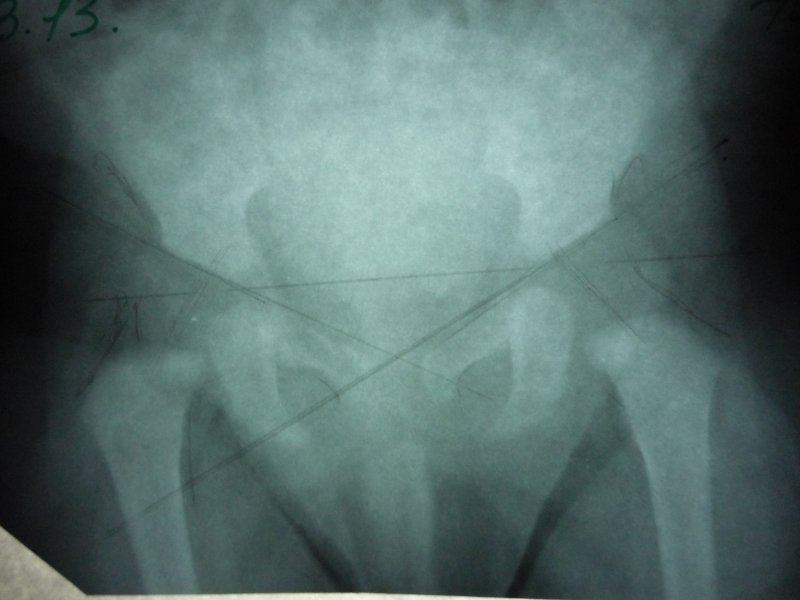

Здравствуйте! посмотрите пожалуйста .Извините за качество ,сам снимок не очень(это один и тот же снимок )

Снимок очень плохого качества, практически не читается. Я не рискну давать Вам рекомендации по такому снимку. Сколько сейчас Вашему малышу?